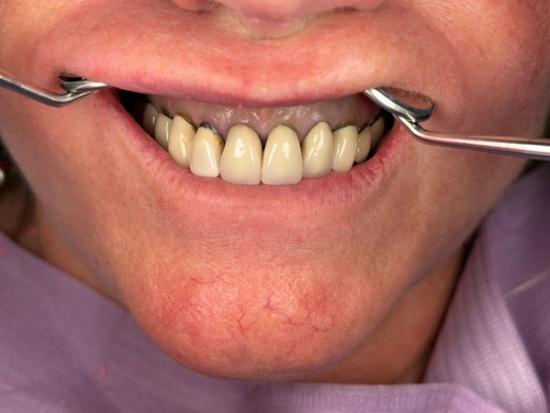

Before Photo

After Photo